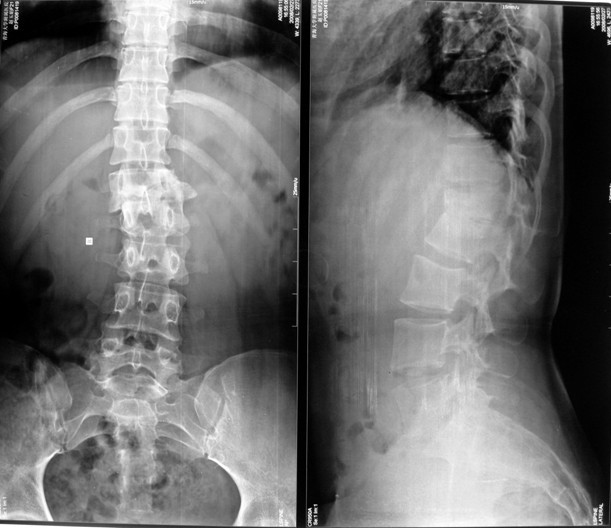

本组手术用时间3~4h , 平均3.5h 。术中出血300~500ml , 平均约350ml 。术后症状完全缓解,无神经功能障碍加重等并发症,1例营养差的老年患者伤口出现窦道,1例因肝功能差,术后未口服抗痨药,伤口出现窦道,经换药后二期愈合,其余病例伤口均一期愈合。马尾神经受损的患者术后基本恢复正常。术后一周后凸角平均 5.4°后凸畸形平均矫正90%以上, 最终后凸角平均8.3°,后凸角度平均丢失4.2°。随访3个月有87%(40/46)有骨痂形成,6个月91.3%(42/46)明显骨性愈合(见图),其余4例9-12个月内愈合,随访时间3-32个月,平均11个月,46例患者中2例在术后2个月和3个月时背部形成脓肿,换药后治愈。2例出院1月后并发结核性脑膜炎,治疗后好转。1例因椎弓根钉偏外,刺激神经根,5个月后从侧方脱出,疼痛加重,因前后路植骨完全愈合,取出后症状完全缓解。

中国学者金大地[22]等采用一期前路病灶清除植骨前路钢板固定治疗腰椎结核,平均18°的后凸畸形得以矫正,Mukhtar[23] AM等采用前路病灶清除植骨分期或同期后路固定治疗腰椎结核22例,术后后凸畸形矫正度数平均为27°。从我们的随访结果看,术后后凸畸形平均矫正度数为26.9°,后凸畸形平均矫正90%以上, 6个月-49个月后随访,后凸角度平均丢失4.2°。本术式也适用于结核所引起的弹性差的后凸畸形,对于病灶纤维化或骨化的非弹性后凸畸形,后路固定后,先行前路病灶、纤维化或骨化切除、松解,逐步刮除病灶、逐步撑开,达到畸形矫正和植骨的目的。